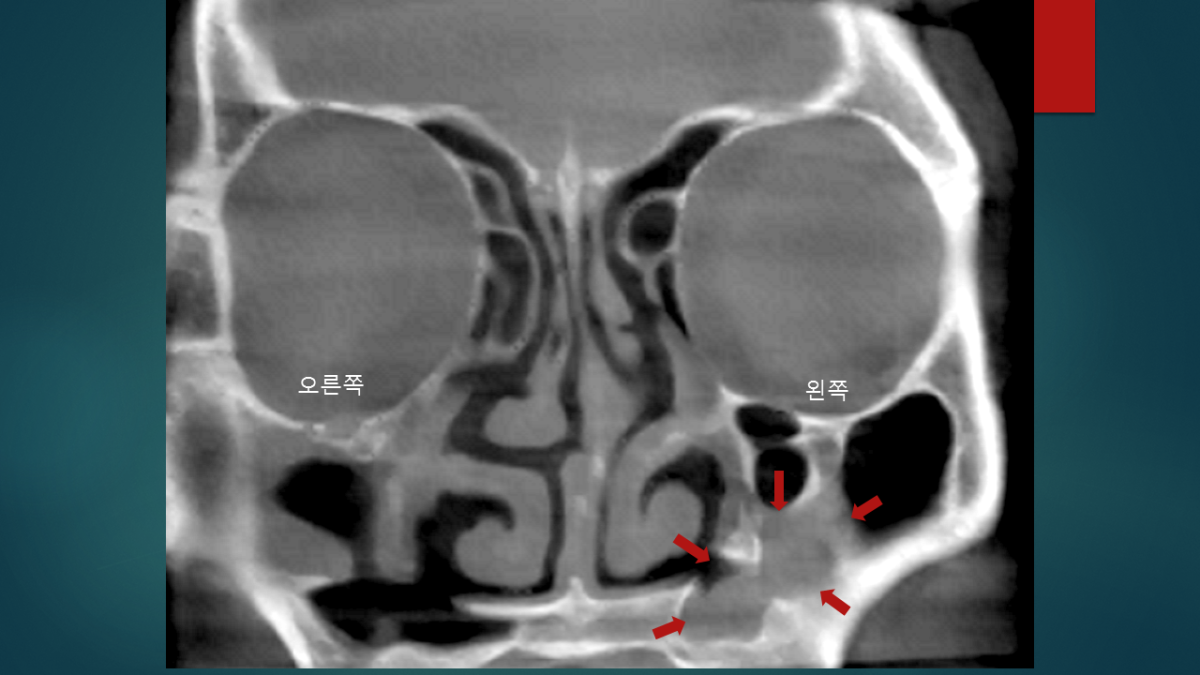

환자분은 대학병원에서 두번의 축농증 수술을 받으셨고, 세번째 재발하여 지난 1월에 코리아이비인후과를 방문해주셨습니다. 내원 당시 좌측의 심한 안면통과 치통을 호소 하셨고 그때 촬영했던 부비동 CT는 다음과 같았습니다.

좌측 상악동의 아래쪽(화살표가 가리키는 부분)으로 뿌연 연조직 음영이 관찰됩니다. 과거 상악동 수술부위의 재발 소견입니다. 내시경으로 봤을때는 지난 축농증 수술시 만들어진 좌측 상악동 아래창 부위를 아래 코선반의 점막이 완전히 막고 있었습니다.